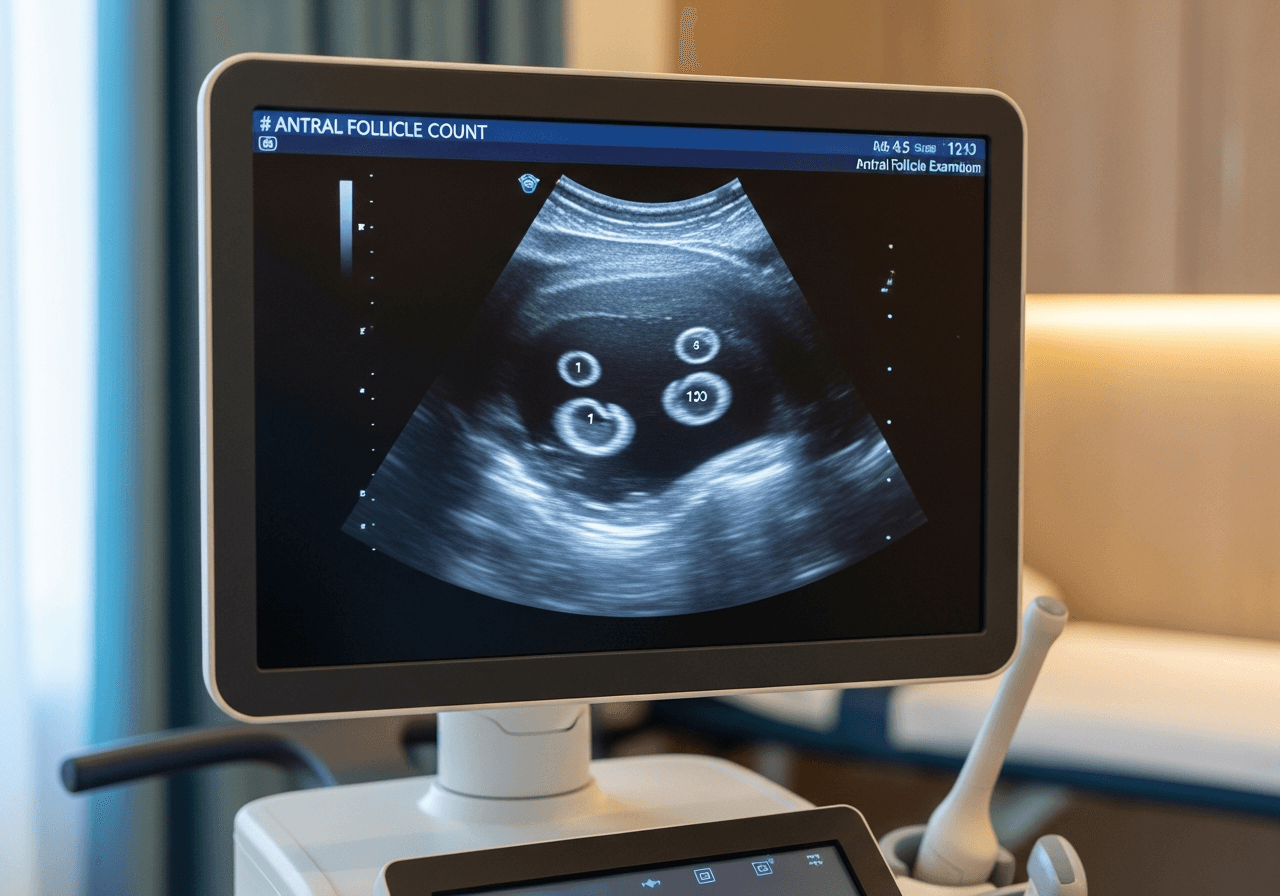

- Échographie de base (J2-J5) : compte des follicules, aspect des ovaires

Un follicule mature mesure environ 18-22 mm au moment de l'ovulation.

L'échographiste mesure les follicules et l'épaisseur de l'endomètre. Ces informations permettent de prédire l'ovulation et d'adapter la prise en charge. Un endomètre d'au moins 7-8 mm et d'aspect triple ligne est favorable à l'implantation.